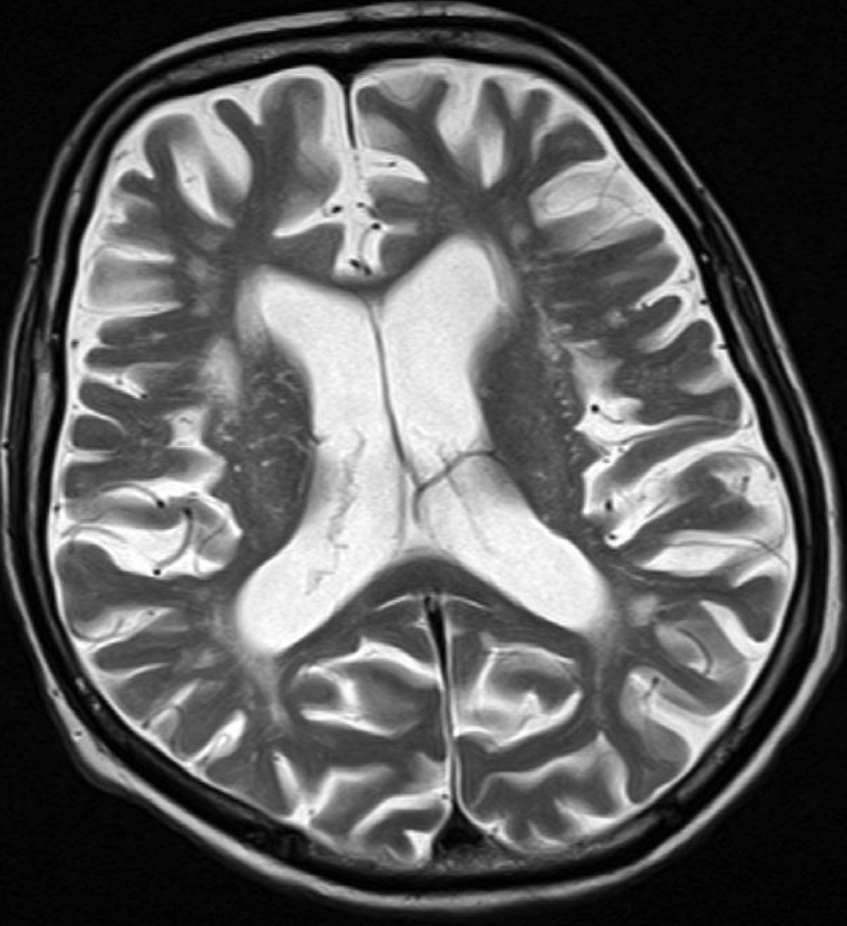

Axial T2-weighted MRI - Cerebral atrophy

showing prominence of the ventricles and generalized widening of

the cerebral sulci in keeping with age-related atrophy.